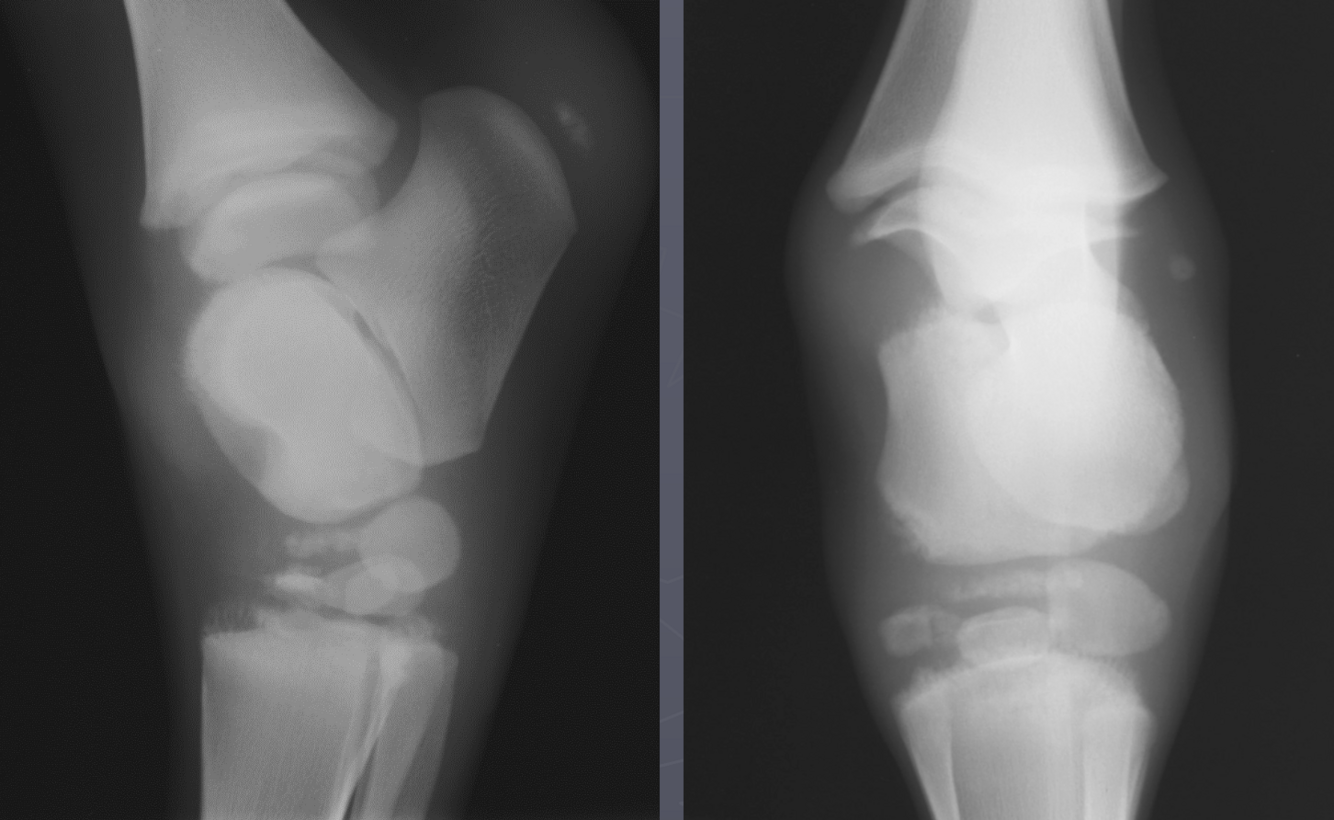

What is shown in these images?

physeal septic arthritis and osteomyelitis -lots of swelling

physeal septic arthritis and osteomyelitis -more focal lesion -asymmetrical swelling